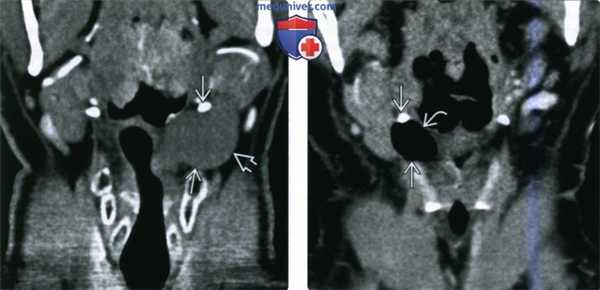

(Слева) При фронтальной КТ с КУ у пациента с объемным образованием передней части шеи, которое увеличивалось при пробе Вальсальвы, слева визуализируется жидкостное ларингоцеле, распространяющееся за пределы гортани (смешанное). Образование проникает через щитоподъязычную мембрану в нижнее подчелюстное пространство.

(Справа) При фронтальной КТ с КУ у другого пациента видна заполненная воздухом полость, следующая через щитоподъязычную мембрану. При таких типах смешанного ларингоцеле требуется открытое хирургическое лечение.